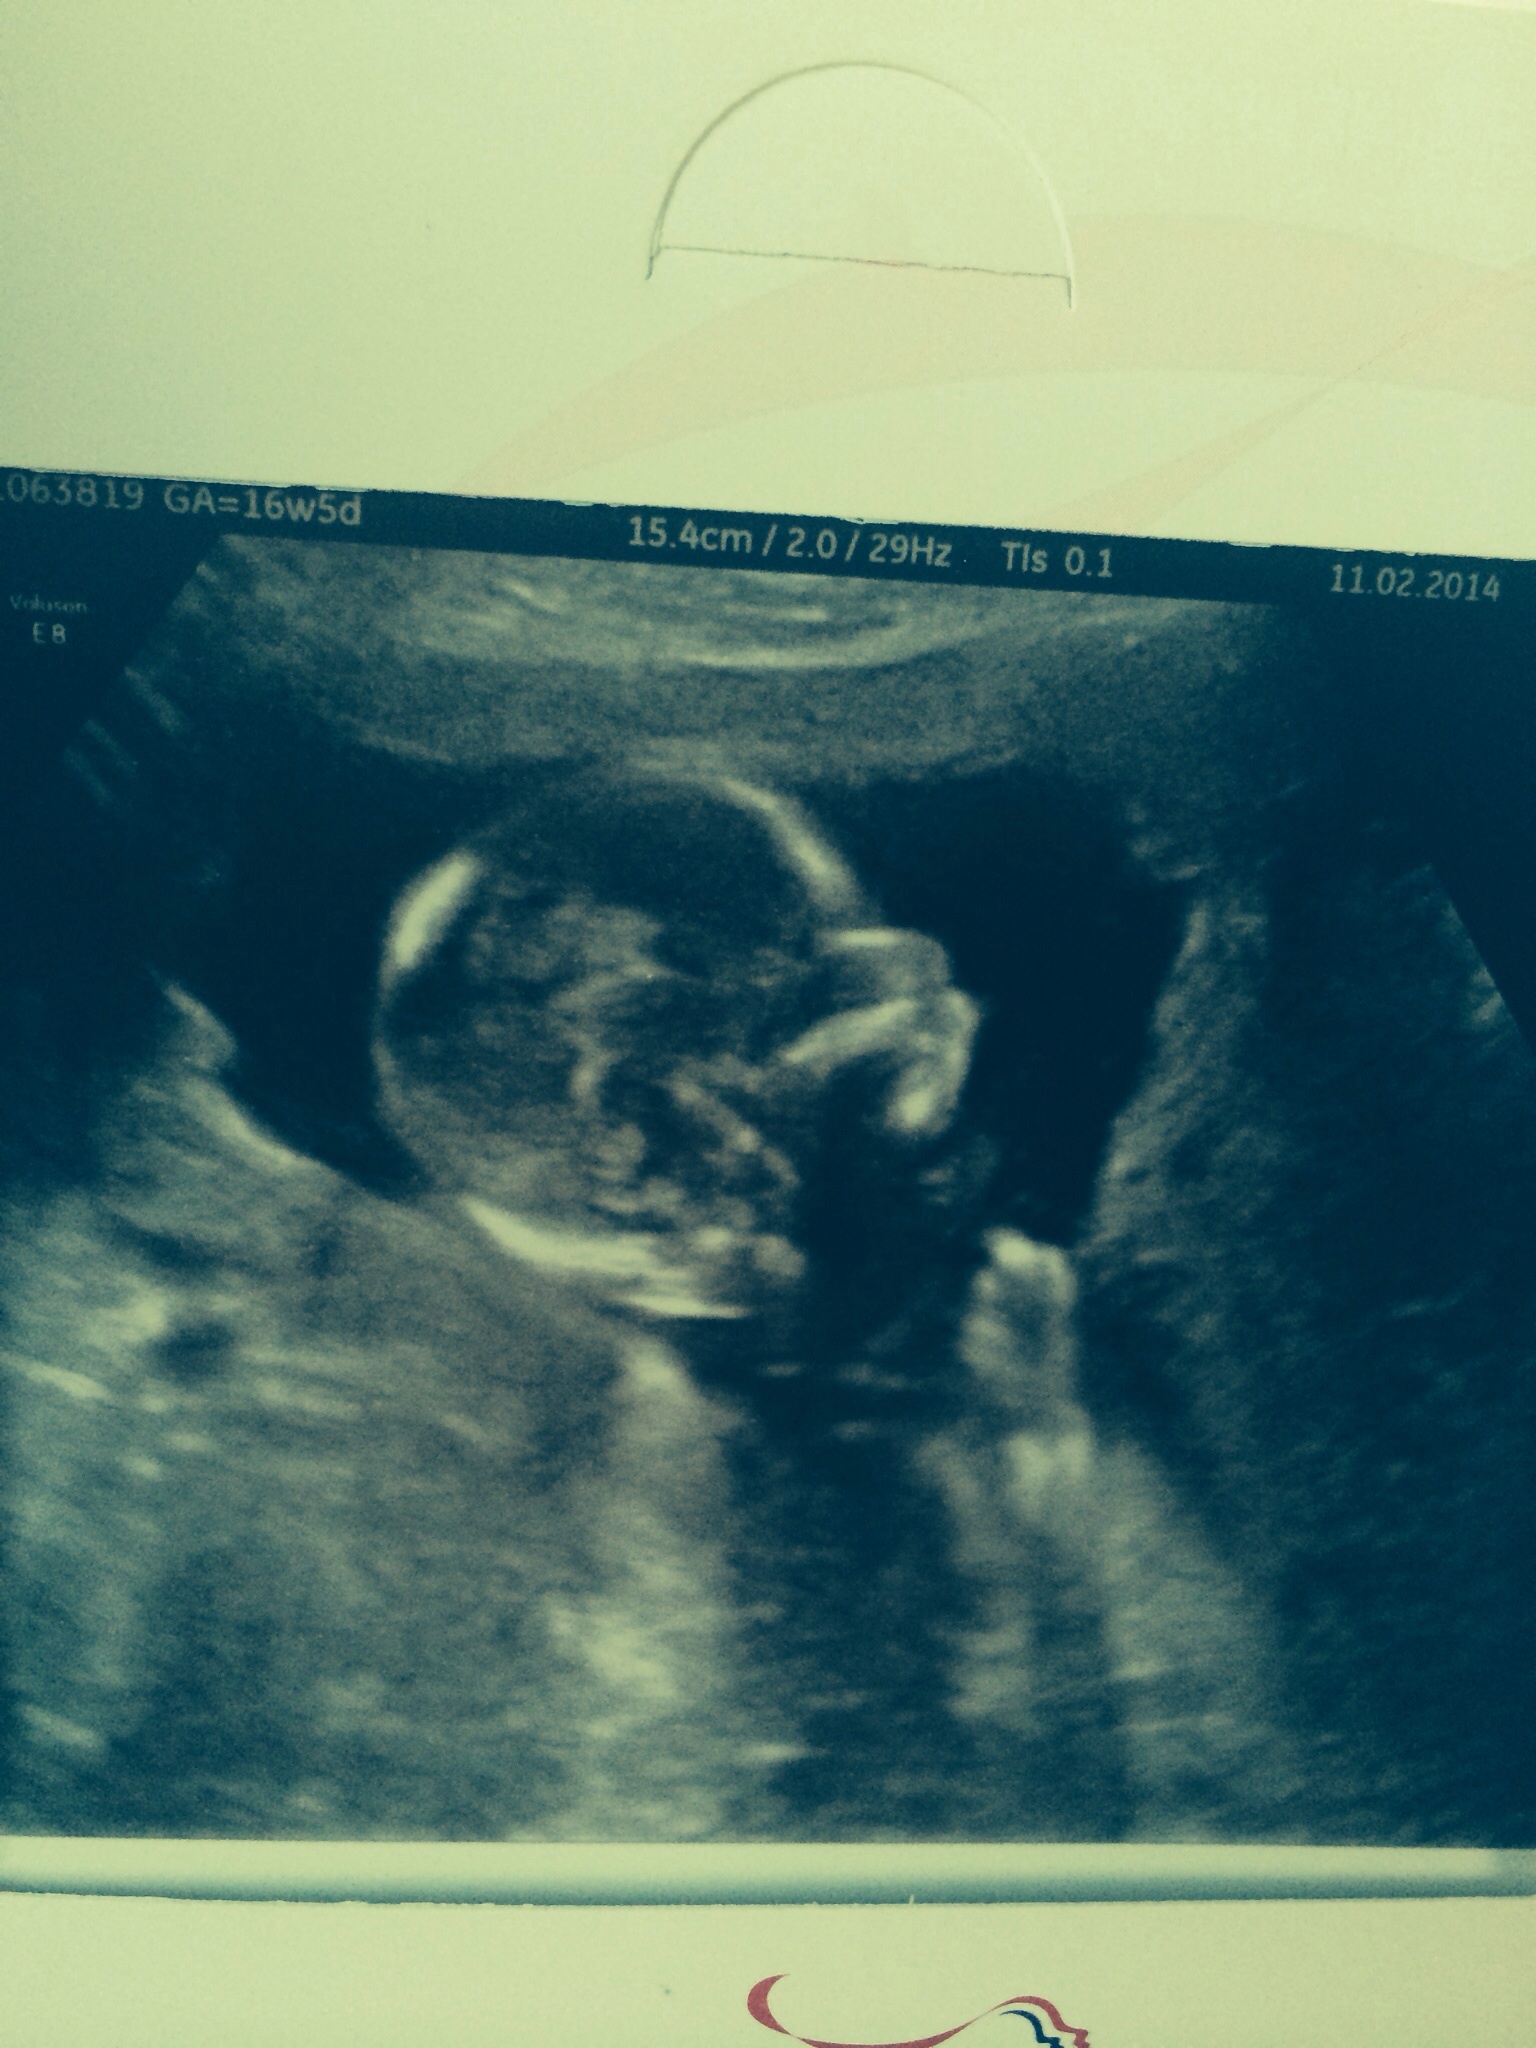

the skull is pretty round leaning girl from the skull picture. keeping ym fingers crossed for you!

I'm driving myself mad looking at the skull shape and wondering if were team blue or pink! Any more guesses?